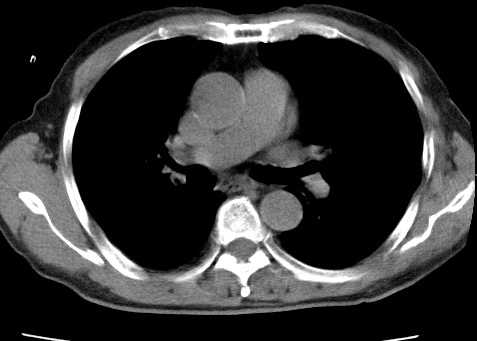

标题: CT24032:男65岁,咳嗽,吸烟20余年,无发热,咳痰 [打印本页]

标题: CT24032:男65岁,咳嗽,吸烟20余年,无发热,咳痰

考虑右肺中叶不张,请大家发表意见

右肺中叶不张、肺门轮廓增大,占位不除外;建议增强,必要时支气管镜详查。

右肺中叶支气管闭塞,中叶肺不张,右侧肺门见肿块影。中心型肺癌的可能大。建议支气管镜检查。

右中叶体积明显缩小,且其支气管未显示,先考虑:中心型肺癌班右中叶肺不张。

建议:支气管镜检查。

考虑右肺中叶中央型肺癌并右肺中叶肺不张;建议:行纤支镜检查。

右肺门旁类圆形肿块影,右肺中叶不张,建议纤支镜检查。

1右肺门旁类圆形肿块影,右肺中叶不张,建议纤支镜检查

2右侧胸膜增厚,右侧叶间胸膜区钙化

3右肺下叶小囊状透亮影考虑肺气肿

平片就可以诊断右肺中叶不张,做CT就是要找原因!中叶支气管开口不清,建议支气管镜检查。